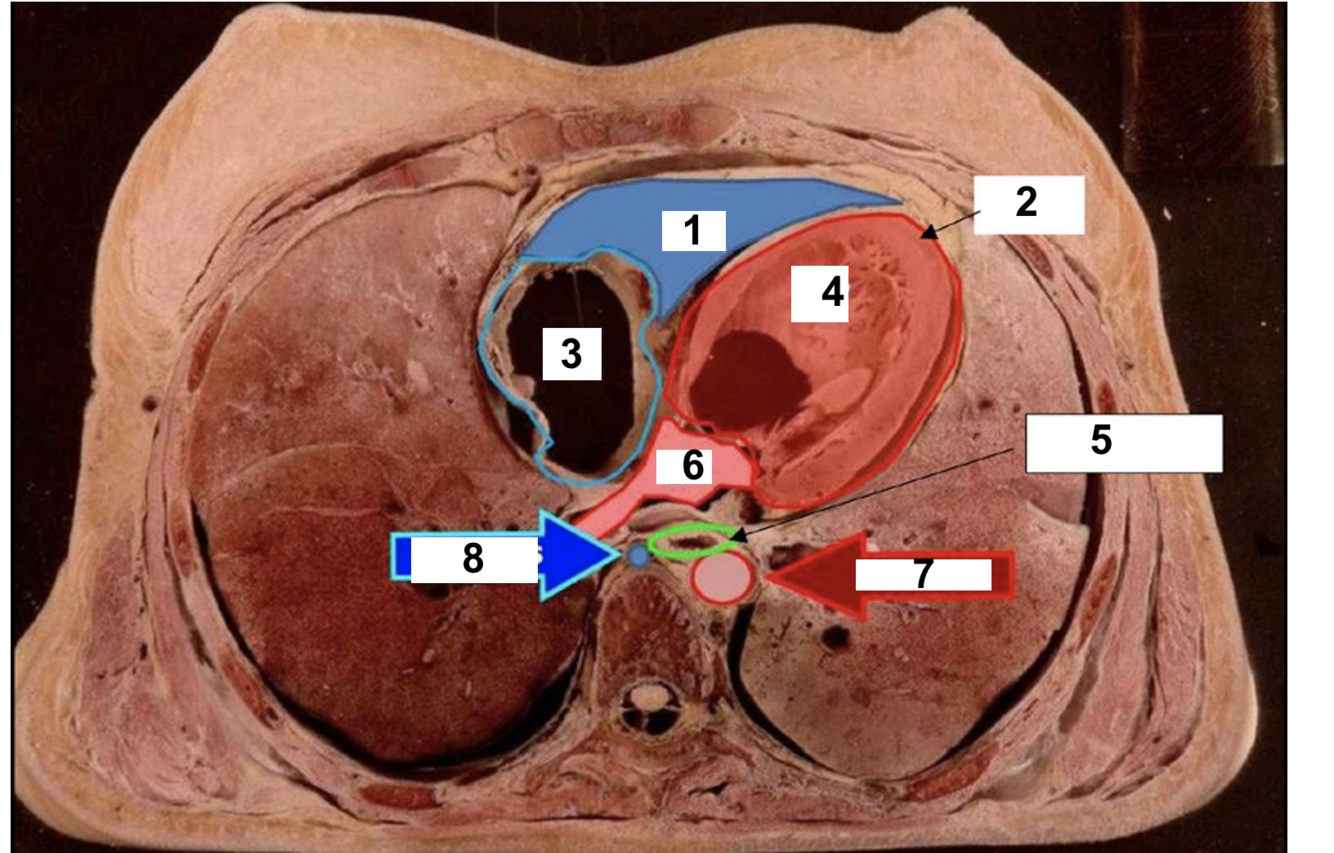

22

1

Apex

23

2.

RV

24

3

RA

25

4

Ascending aorta

26

5

LA

27

6

Descending aorta

28

7

LV

29

8

oesphagus